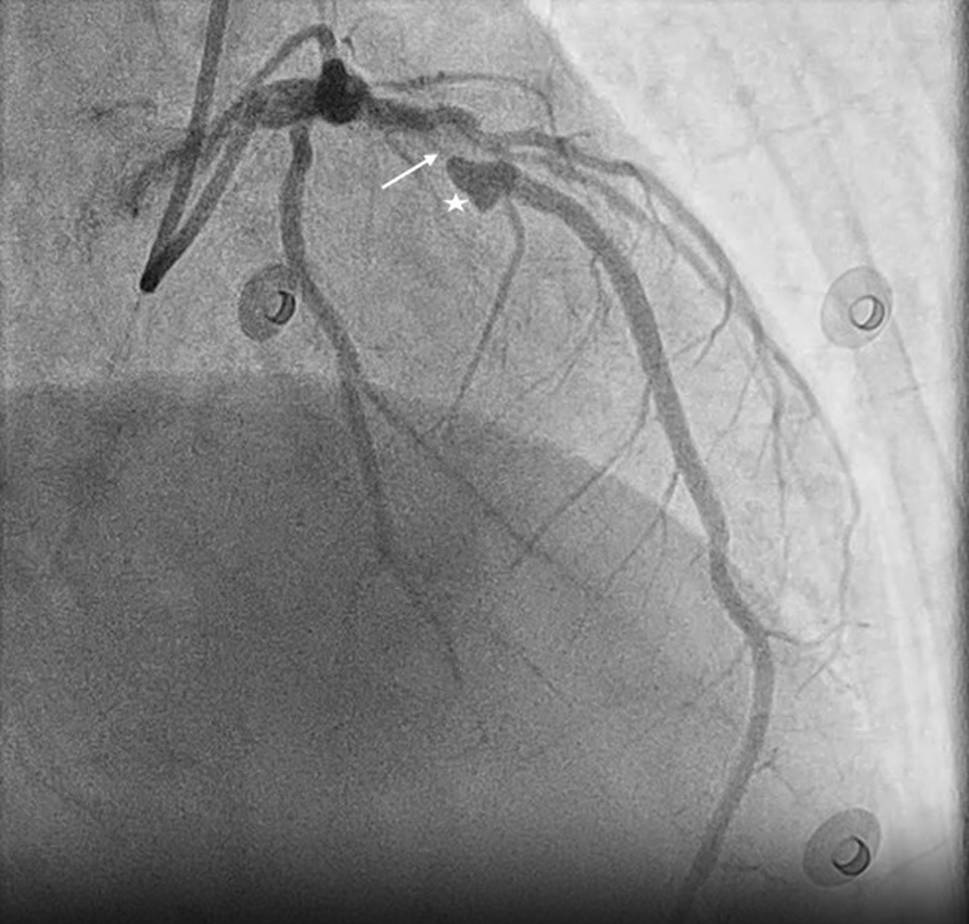

A 72-year-old woman with a history of hypertension and recently diagnosed heart failure underwent invasive coronary angiography, revealing a significant lesion of the left anterior descending with a heart-shaped aneurysm (Fig. 1). Following multidisciplinary Heart Team discussion, she underwent a successful percutaneous coronary intervention.

Heart-shaped coronary artery aneurysm indicated by a star, left anterior descending indicated by an arrow